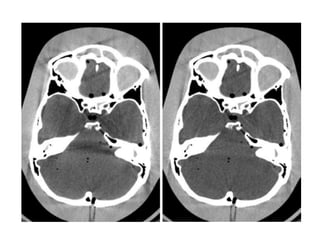

BEAM HARDENING ARTIFACT

• In the head, a so-called "cup artifact" may be produced.

ARTIFACTS BEAM HARDENING ARTIFACT •Heterochromatic X-Ray beam passes through the patient, the low energy protons are rapidly absorbed. • The µ of a tissue near the beam entry site will be higher than the µ of the same tissue after the beam has been hardened by passage through a volume of tissue. • Reconstruction programs anticipate and correct for variation in µ caused by beam hardening, but such corrections are not precise • In the head, a so-called "cup artifact" may be produced. • Beam hardening reduced by filtration (pre-hardening), beam hardening correction software & calibration correction.